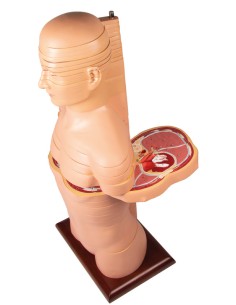

3B Scientific, Torse bisexuel, modèle de luxe, séparable en 20 parties B32

3B Scientific, Torse bisexuel, modèle de luxe, séparable en 20 parties B32

3B Scientifique, torse bisexuel japonais, décomposable en 18 parties B32/4

3B Torse scientifique, africain bisexuel, décomposable en 24 parties B37

3B Scientific, mini torse humain sans tête, décomposable en 9 parties B20